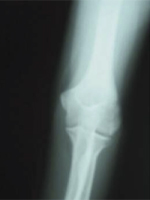

第24診(固定後61日目):レントゲン撮影。骨折部治癒(図8,9)。

図8 61日目X線 正面像 |